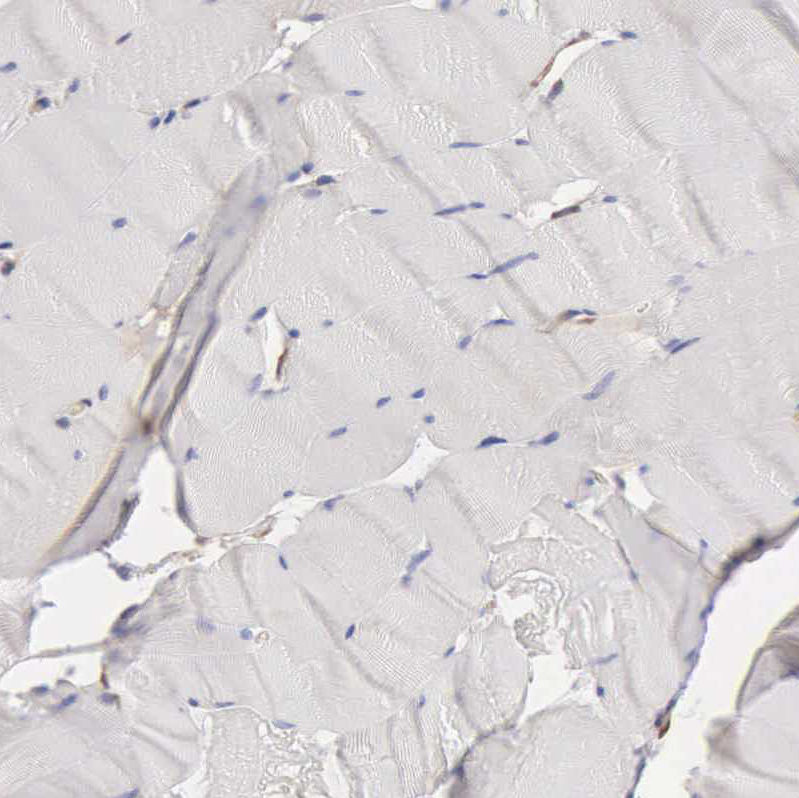

Immunohistochemistry analysis in human cerebral cortex and skeletal muscle tissues using HPA001078 antibody. Corresponding APOL2 RNA-seq data are presented for the same tissues.